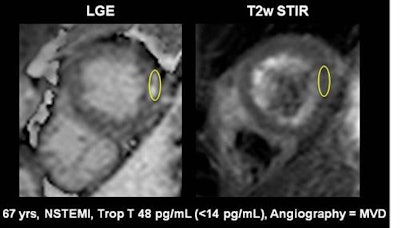

The group concluded that native T1 and T2 mapping are far superior to standard T2-weighted images and extracellular volume fraction for distinguishing acute from chronic myocardial infarction. And importantly, "native T1 and T2 values may be used as activity markers, enabling identification of culprit lesions in myocardial infarction and multivessel disease," Tahir said.